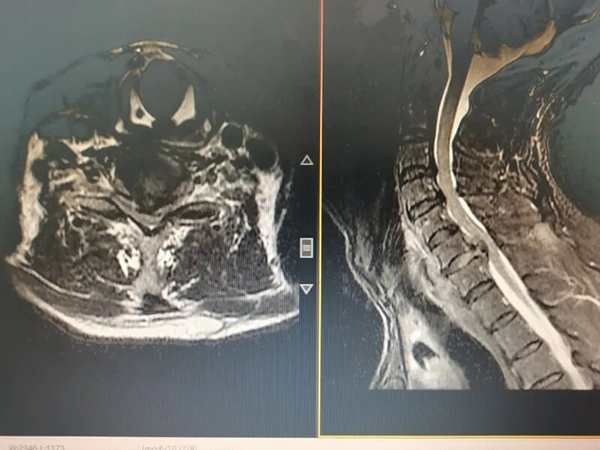

接诊后,张明主任团队立即为刘大爷完善颈椎影像学等相关检查,检查结果显示:刘大爷存在多节段颈椎间盘突出伴椎管狭窄,其中C6-7节段突出物已严重压迫左侧神经根及脊髓,这正是导致他颈痛、手麻的 “罪魁祸首”。

手术当天,一切准备就绪。张明主任团队为刘大爷实施了内镜下颈椎后路间盘切除椎管减压术,在其颈部后方做2 处仅1厘米的微小切口,将内镜系统精准置入病变节段,高清内镜下,突出的椎间盘组织、增生的骨赘及受压的神经清晰可见。